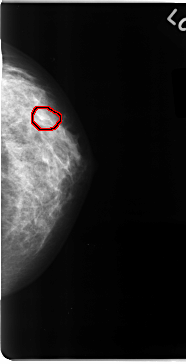

C_0090_1.LEFT_MLO

LEFT_MLO LINES 4688 PIXELS_PER_LINE 2568 BITS_PER_PIXEL 12 RESOLUTION 50 OVERLAY

FILE: C_0090_1.LEFT_MLO.OVERLAY

TOTAL_ABNORMALITIES 1

ABNORMALITY 1

LESION_TYPE CALCIFICATION TYPE PLEOMORPHIC DISTRIBUTION CLUSTERED

ASSESSMENT 4

SUBTLETY 4

PATHOLOGY MALIGNANT

TOTAL_OUTLINES 1

BOUNDARY